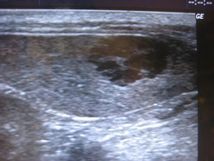

| 超音波で確認すると、脾臓の部分に黒い影が写っています。 正常な脾臓だと黒い影が写ることがないので、ここに腫瘍があることが分かります。 |